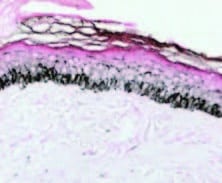

REDUKTION DER EPIDERMALEN MELANINDICHTE 1 WOCHE NACH MIKRONEEDLINGVERFAHREN

Cassiano et al., Indian Journal of Dermatology, Venereology and Leprology | Band 85 | Ausgabe 6 | November bis Dezember 2019